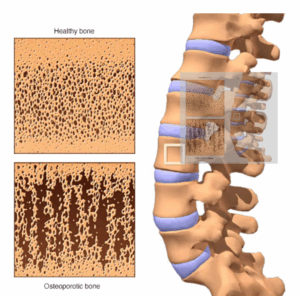

Osteoporosis

Osteoporosis causes bones to become weak and brittle — so brittle that a fall or even mild stresses such as bending over or coughing can cause a break. Osteoporosis-related breaks most commonly occur in the hip, wrist or spine.